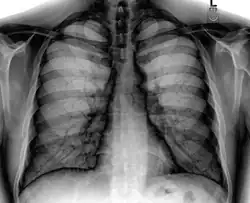

Chest X-ray PA inverted and enhanced.